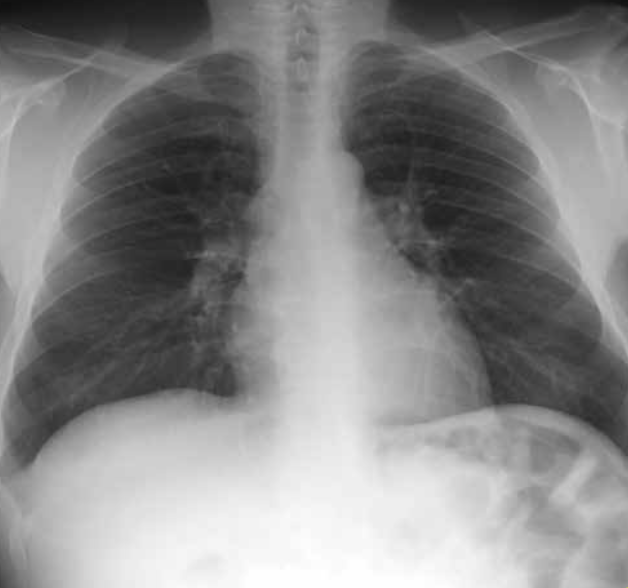

Observa y nombra la silueta de las diferentes estructuras que forman el mediastino en radiografía lateral.

Mediastino en radiografía lateral.

A: Corazón. B: Cayado aórtico. C: Tráquea. D: Hilio. E: Ángulo costofrénico. F: Diafragma izquierdo. G: Diafragma derecho. H: Hígado. I: Burbuja gástrica.